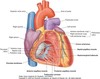

What does the base of the heart consist of?

- the left atrium

- a small portion of the right atrium

- the proximal parts of the great veins (superior and inferior venae cavae and the pulmonary veins)

Where is the base of the heart directed?

It is quadrilateral and directed posteriorly + fixed posteriorly to the pericardial wall

Oesophagus lies immediately posterior to the base

What is the apex of the heart formed by and where is it positioned?

Positioned deep to the left fifth intercostal space, 8-9 cam from midsternal line

Formed by the inferolateral part of the left ventricle

What does the anterior surface face and consist of?

- Faces anteriorly

- Consists mostly of right ventricle

- Has some of right atrium on right

Has some of left ventricle on the left

In the anatomical position, what does the heart rest on?

- The diphragmatic surface

What does the diphragmatic surface consist of?

- Consists of left ventricle + small portion of right ventricle

- Rests on the diaphragm

Why does the left ventricule have a thicker muscular wall than the right?

More force is required to pump blood through the bdy than through the lungs

How does the blood return to the right atrium?

Enters through 1 of 3 vessels:

- Superior + inferior venae cavae -> together deliver blood to heart from body =

- coronary sinus -> returns blood from heart walls

Where does the superior and inferior vena cava enter the right atrium?

- Superior vena cava -> enters upper posterior portion of right atrium

- Inferior vena cava + coronary sinus enter lower posterior portion of right atrium